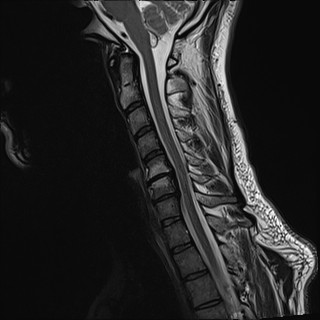

Wirbelsäule HWS

t1_tse_sag